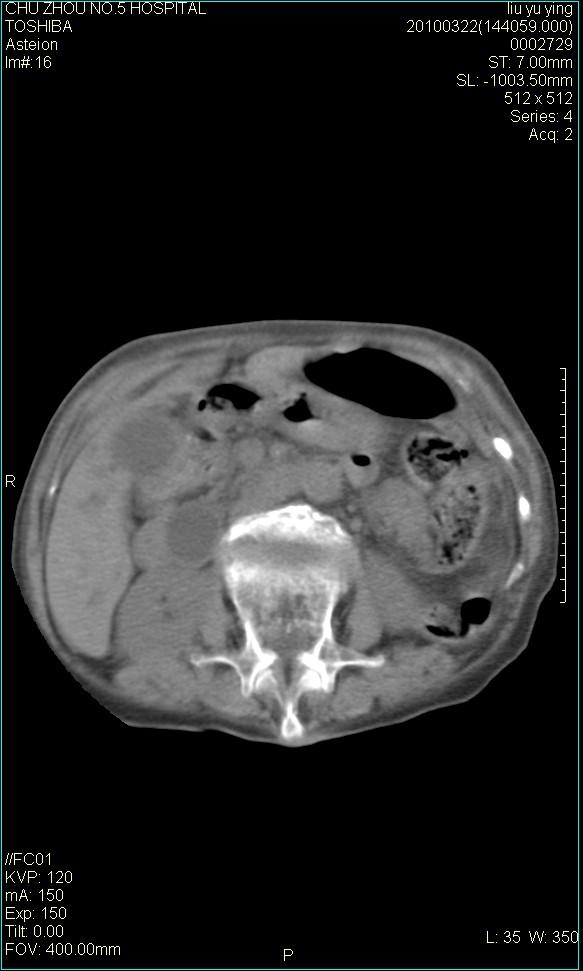

以下是引用科室第一人在2010-3-23 6:50:00的发言:[br]胆总管下段梗阻,多为肿瘤性病变,巨形胆囊,胆囊炎胆囊窝积液。[br]双侧胸腔积液,右降

以下是引用随光逐影在2010-3-23 8:12:00的发言:[br]1)胆系低位梗阻(肝内外胆管扩张,胆囊增大),原因待查。2)胆囊炎。3)双侧少量胸腔积液。4)降主动脉迂曲。